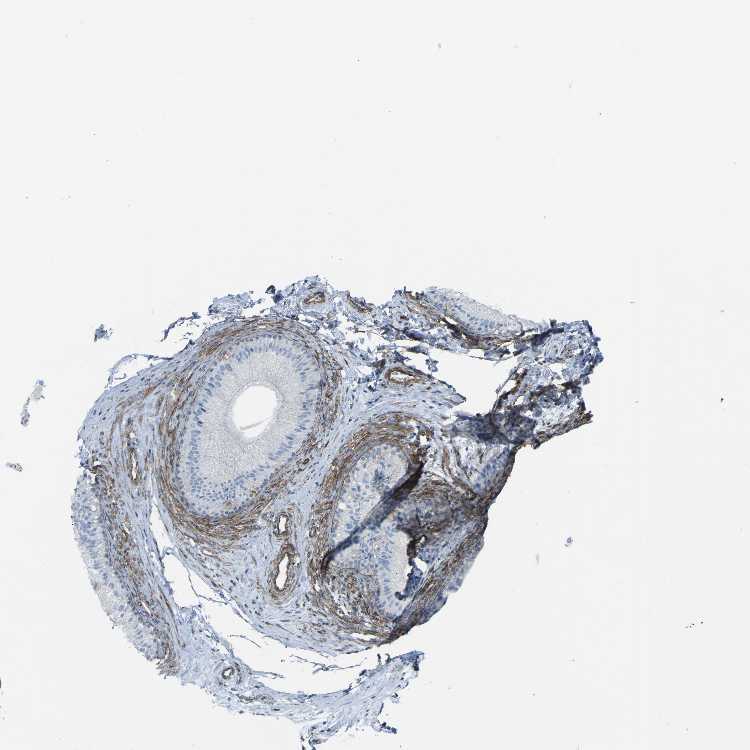

TISSUE PRIMARY DATA EPIDIDYMIS Show tissue menu

EPIDIDYMIS - Antibody stainingi

Antibody staining in the annotated cell types in the current human tissue is reported as not detected, low, medium, or high, based on conventional immunohistochemistry profiling in selected tissues. This score is based on the combination of the staining intensity and fraction of stained cells.

Each image is clickable and will lead to virtual microscopy that enables deeper exploration of all samples and also displays staining intensity scores, fraction scores and subcellular localization as well as patient and tissue information for each sample.

Antibody HPA018894Antibody CAB016348

Glandular cells LowNot detected